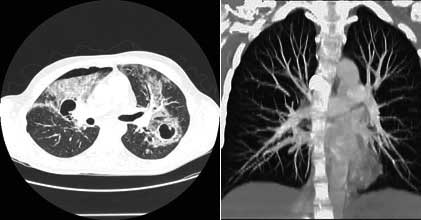

CT screening (rano otkrivanje) karcinoma pluća

Karcinom pluća je najčešći karcinom kod muškaraca, pa se ranom otkrivanju te bolesti pridaje velika važnost. Uvođenje višeslojnog CT-a (MSCT) u kliničku praksu omogućilo je i screening (rano otkrivanje) karcinoma pluća. Pregled je namijenjen onima koji su visokog rizika za karcinom pluća i omogućava otkrivanje izrazito malih čvorova u plućima, koji mogu biti prisutni, a da nisu vidljivi na standardnom rtg snimku pluća. Rano otkrivanje ovih promjena može dramatično poboljšati uspješnost liječenja karcinoma pluća.

Kome je potrebno ovo snimanje?

CT screening pluća se preporučuje uraditi pušačima starijim od 60g, a čiji pakovanje-godine index je veći od 10 (pakovanje-godine index se dobije tako što se pomnoži broj godina pušenja sa brojem kutija cigareta koje se ispuše svaki dan: preko 80% karcinoma pluća se dijagnostikuje u ljudi starijih od 60g). Drugi kandidati za pregled su pacijenti starosti 50-60g, koji imaju pakovanje-godine index 20-30 ili s drugim riziko-faktorima kao što je izlaganje azbestu ili hronična opstruktivna bolest pluća.